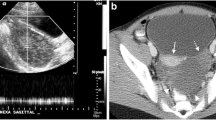

A 16-year-old patient was admitted in our emergency department with persistent abdominal pain in her right lower abdominal quadrant. The patient claimed that the pain was colic like, persistent and gradually advancing the last 2 months. Her medical history was free, her menarche was in the age of 13 years and her menstrual cycle had a periodicity of 28 days. The clinical examination revealed a palpable abdominal mass extending from the fossa iliaca to the liver. The patient was hemodynamic stable. After two doses of intravenous paracetamol the pain was alleviated. We performed a radiologic and laboratory control; our imaging control included an Ultrasound of the lower abdomen and a Ct Scan of the upper and lower abdomen. An intravaginal ultrasound control could not be performed because the patient was still virgin. The CT scan revealed a cystic lesion 23x15cm located in the right oblique abdominal area, from the liver to the minor pelvis, which is causing pressure to the right kidney and the bladder and a small fluid collection in the Douglas region. (Fig. 1) This finding combined with the laboratory values, which showed an elevated CA 125 marker of 57,9 and a normal function of the hepatobilliary and the urinary system, led us to make a decision to perform a laparotomy. We performed a subumbilical incision of the abdomen. The ovary was identified, it was very swollen and there was fluid in the rightovarian pedicle. This specimen was taken for cytologic examination, which was negative for malignancy. An incision of the ovarian mass followed in order to make it possible to remove the ovary from the abdomen. The structure was bulky without any fluid and the excision was very difficult. Intraoperatively, after performing a light traction of the ovary a triple partial torsion of the ovarian pedicle was seen, nevertheless, there were no signs of ischemia or necrosis of the ovary. After careful preparation of the ovary and the pedicle we performed the excision and the specimen (excised ovary) was sent as a frozen section material for histopathologic examination (Fig. 2). The result was negative for malignancy and was compatible with normal ovarian tissue. The left ovary had a normal anatomy without any evidence of pathology or dysfunction. Macroscopically, the excided ovary was a kidney-like, very oedematous structure 23x14x5 cm. There was no sign of necrosis or hemorrhage, but there were many cystic lesions on the upper surface of the ovary, with a maximum diameter of 1.5 cm and a serous content (Fig. 3). Afterwards we performed an appendectomy. The patient recovered very fast postoperatively, without any pain and symptoms. The pathologic examination revealed a stroma oedema with presence of many fibroblast and collagen fibre, cystic ovarian folicules with lutenization in the periphery of the ovary without any stromal changes (Fig. 4). In the appendix many parasitic worms were present of the type of Enterobius Vermicularis.